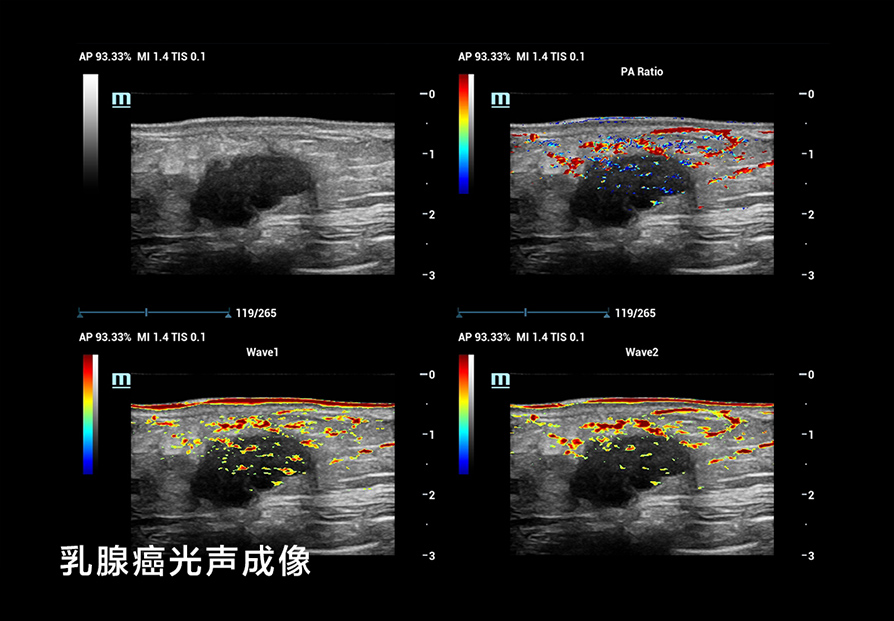

我们在 B-Mode 成像方面考虑了更细(超高频率)、更深(超低频率),更好的对比分辨率,如个异化的 HD Scope,以提高早期鉴别诊断的能力;在超微血流方面, UMA突破传统彩色多普勒的限制,使细微血流的显示达到新的高度;还有创新的血流流变学(VFM)等分析技术,以及流变学与生物力学结合的技术等;在弹性成像方面,我们也有很多可圈可点的地方。我们可以形成多模态,多模式的成像与显示,为临床和科研提供新的工具;在造影成像(CEUS)方面,我们还有极具特色的高帧率造影技术和 CEUS QI 分析系统,还有光声成像等这些新的方向。

A:超声有很多物理限制,和放射学有物理限制一样,核磁共振也有它的局限性。如何用新的技术来弥补和解决这些局限性,再用各种方法把他综合到最好,这是一个很难的事情,但再难也要想办法解决。举例来说,我们发展了 33 兆的探头做造影。我们扫描了虹膜的微灌注血管,当看到成像后,我们都很惊讶。因为虹膜在眼睛的最前面,是最小的血流,但我们能把它显示出来。而造影是一个系统工程,要同时发展造影剂,还要发展跟造影剂相关的技术。我们需要与负责造影的工程师和科学家密切地沟通,才能把造影剂最有效的成分提取出来。我们和团队的资深科学家一起,在这方面做了很多探索。

我们还用了一个技术,在医院里看到乳腺病灶类的微钙化灶,这些极小的微钙化灶,原来超声是看不见的,只有钼靶才能看到。但能看见微钙化灶对乳腺癌的早期鉴别诊断至关重要。钼靶在乳腺微钙化灶方面有非常细的分类,对早期鉴别诊断提供了非常有意义的指导作用。如果我们持续发展这个超声技术,把它用在日常的临床工作中,那医生就能够更早地发现乳腺病灶的早期微钙化。